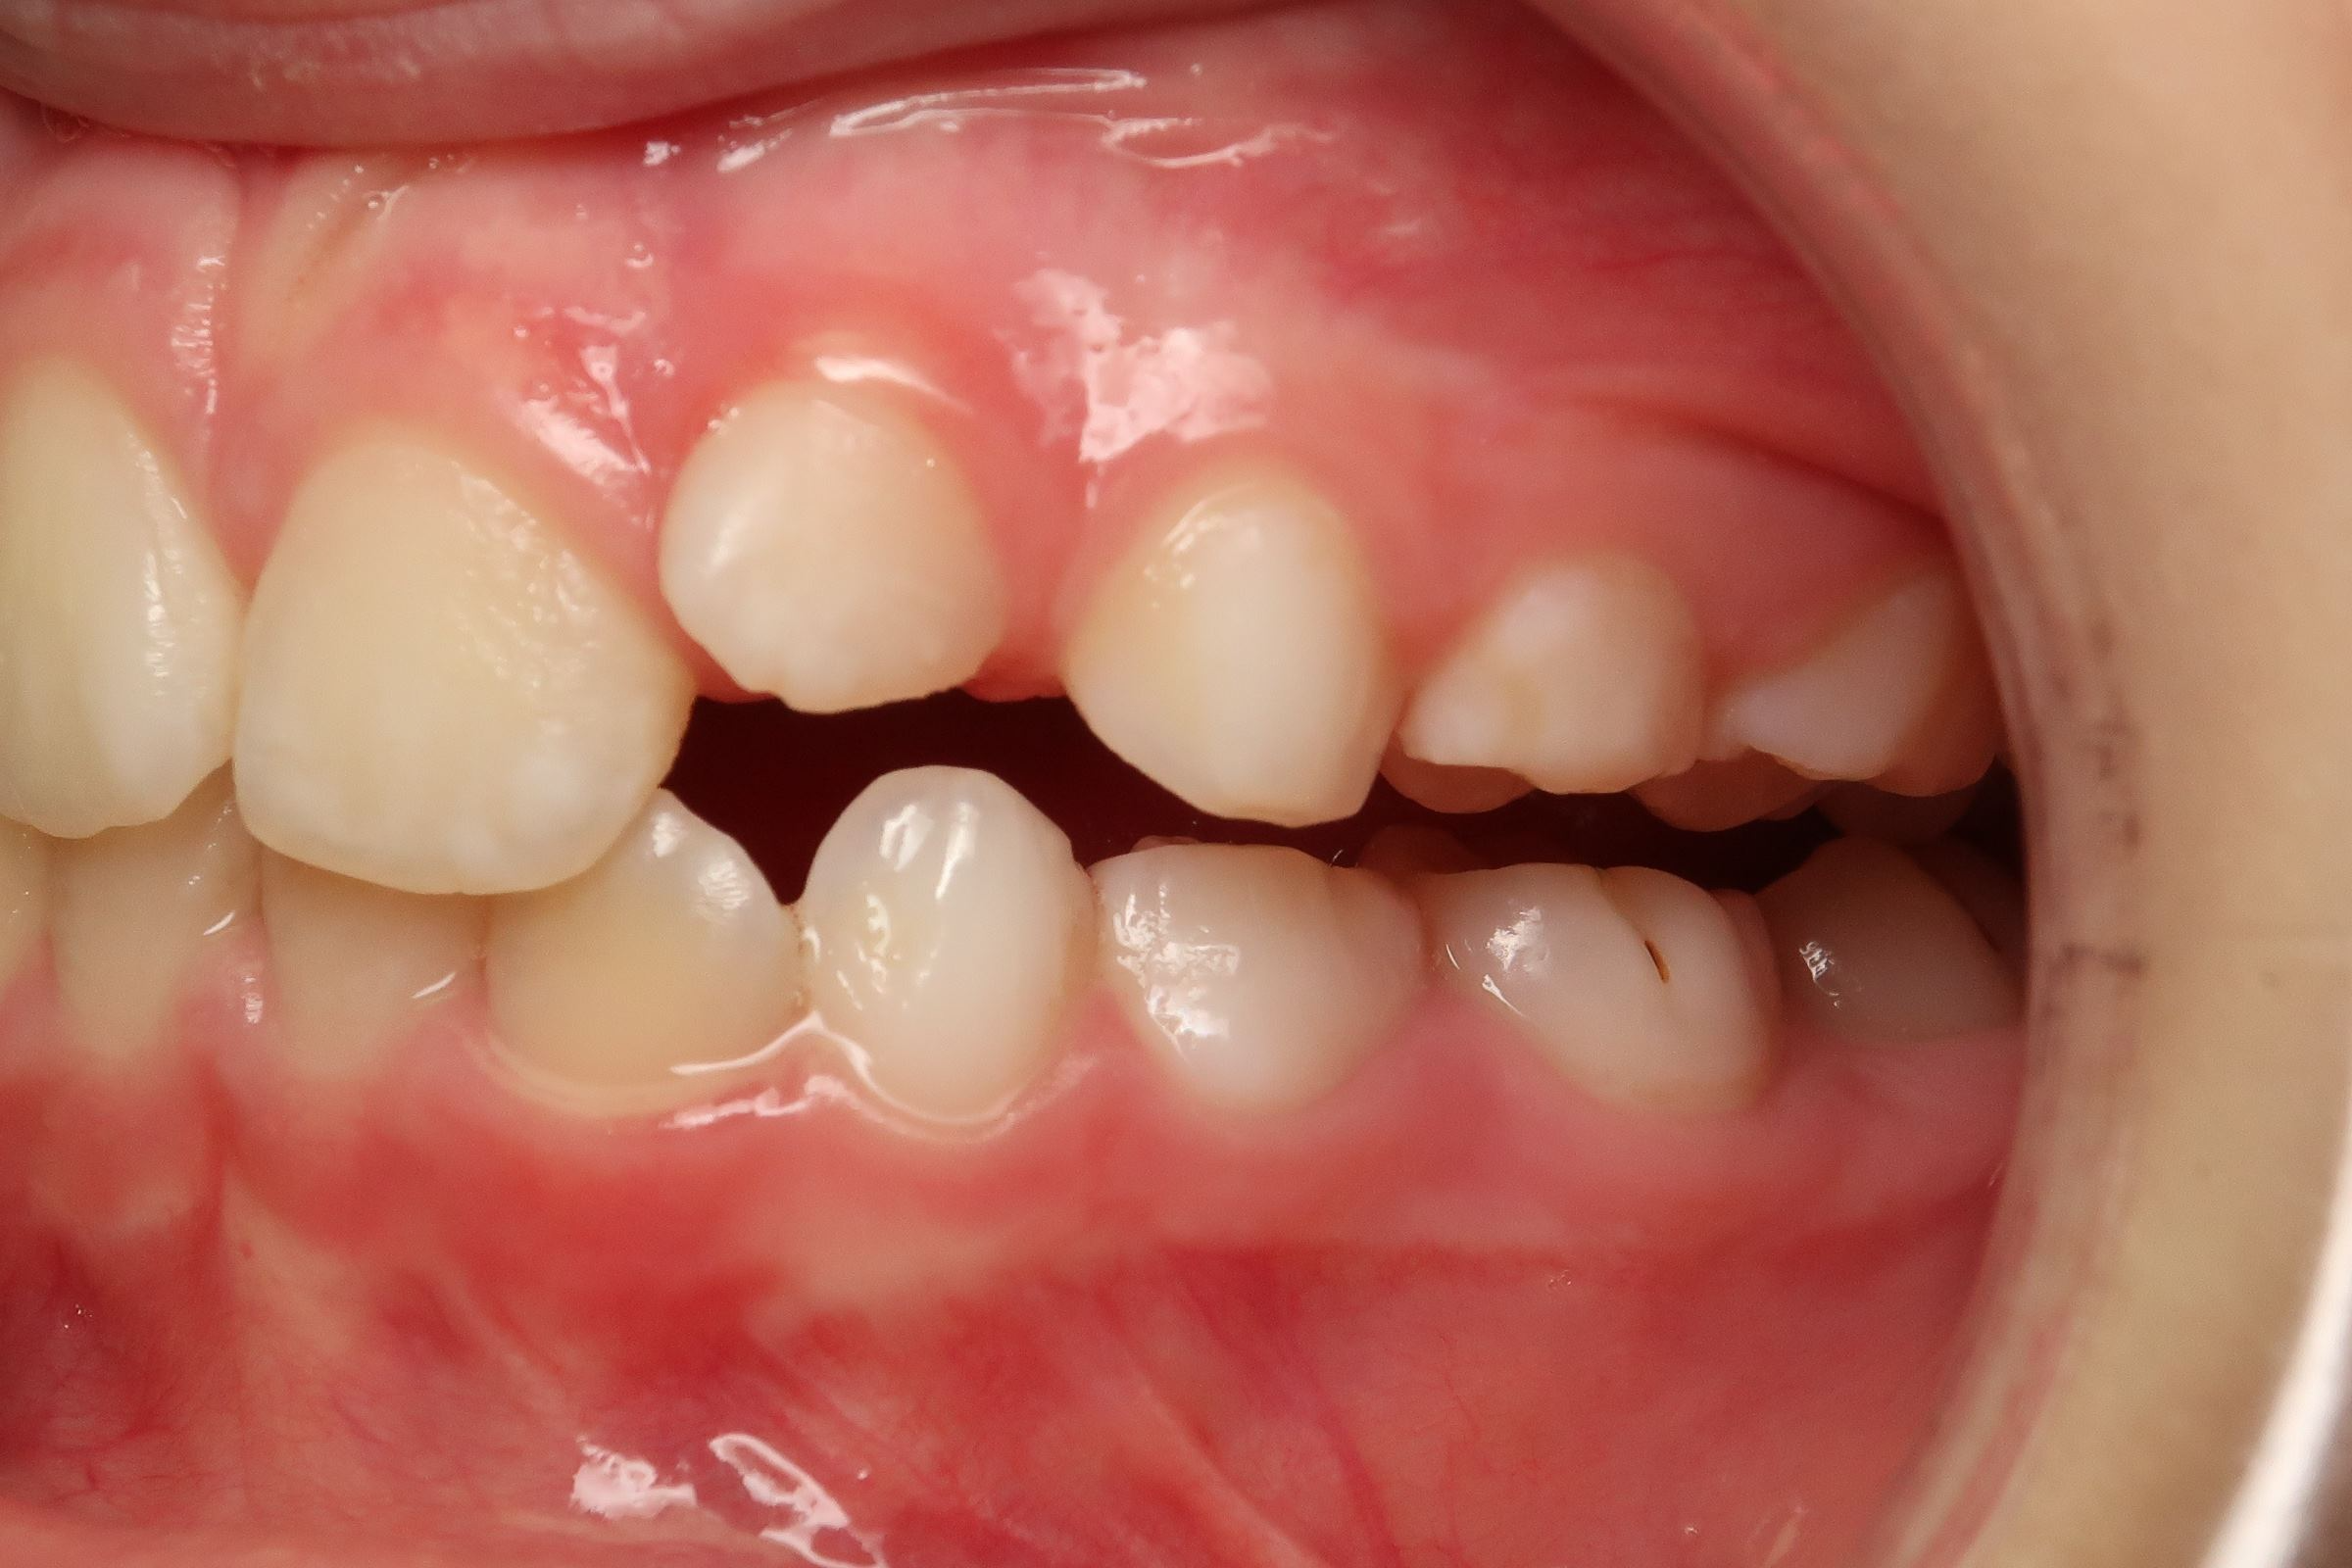

appareillage mobile pendant 13 mois

surveillance de la dentition pendant 16 mois

bilan début et en cours de traitement